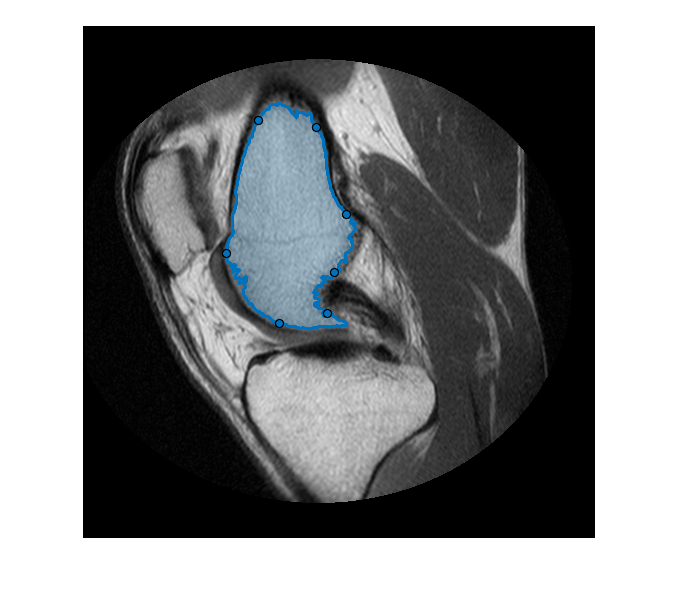

フリーハンド ROI の作成

セグメンテーション マスクの形状に従うフリーハンド ROI を作成します。このプロセスの詳細については、フリーハンド ROI を使用したセグメンテーション マスクの調整を参照してください。

MRI イメージをセグメント化し、マスクから最も大きい 2 つの領域を選択します。

segmentedLabels = imsegkmeans(im,3); boneMask = segmentedLabels==2; boneMask = bwareafilt(boneMask, 1);

セグメント化された 2 つの領域の境界の座標を取得します。

blocations = bwboundaries(boneMask,'noholes');

bwboundaries によって返される位置を x、y の順に変換します。

pos = blocations{1};

pos = fliplr(pos);

セグメント化されたマスク内にフリーハンド ROI を作成します。

hf = drawfreehand('Position', pos);